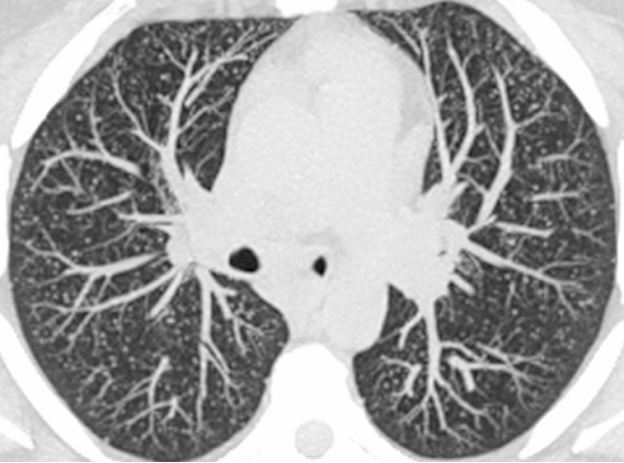

随机(粟粒状):整个肺部均匀分布

○  叶间裂/胸膜分布可以发生, 但不具备聚集特点。也就是说, 随机分布结节的胸膜受累/分布不像周围淋巴分布结节那么明显

2c83c8787296f49a1673d08986fa5f89.png

随机分布结节彩图示意, 白色球为肺结节。